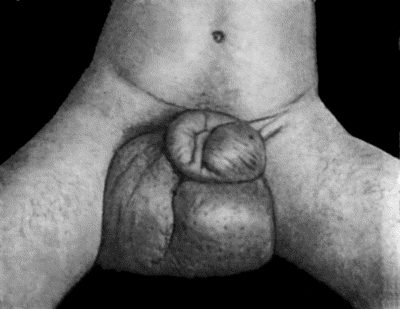

98.Elephantiasis of Penis and Scrotum 388